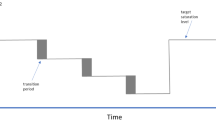

The depth-based tidal volume exhibited a high degree of correlation (R = 0.92). However, the resulting line of best fit, although distinct in nature, deviated markedly from the line of unity. However, the strong linear relationship that was observed indicates the potential for TVdepth to be a reliable trend monitor for tidal volume. To further investigate this, we constructed a concordance plot where the difference between the two parameters over a running time window (ΔTVdepth and ΔTVvent) are plotted against each other [24]. We can see from the resulting concordance plot (Fig. 7) that the majority of data lie in the top right hand and bottom left hand quadrants, indicative of a strong trending behaviour. A concordance value can be computed by counting the number of data points in these two quadrants relative to the total data count. The concordance was found to be 0.88 for these tidal volume data indicating a high degree of trending between the two signals. It may be possible to construct a mapping from TVdepth to the actual tidal volume through a correction factor, however, achieving this in practice may be non-trivial due to need to account for various patient postures, the boundary morphology of the ROI, the presence of blankets, etc.